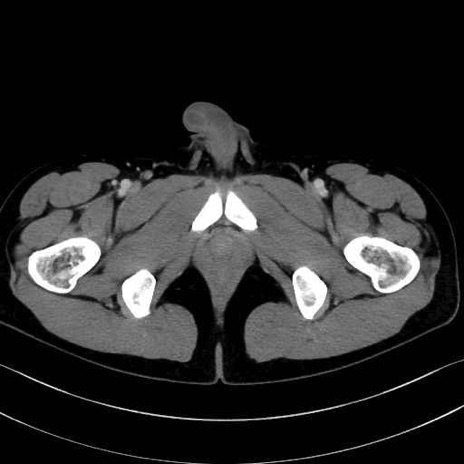

精嚢(seminal vesicle)のCT画像における解剖

症例

【症例】20歳代 男性 スクリーニング